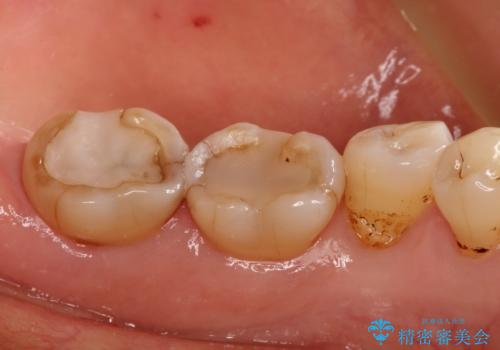

- 以前治療したところがしみて、アイスが食べられないから被せものの治療をしてほしいと来院された患者様です。

咬合が強く、歯牙にマイクロクラックが入っている状態でした。歯髄は保存可能と診断され、フルジルコニアクラウンによる治療を行いました。

咬合面に広範囲の修復物がある状態で中心に強い力が加わると歯牙は外方性の歪みが生じ、マイクロクラックができます。これを防ぐには、咬頭被覆するアンレー、もしくはクラウンによる治療が必要です。